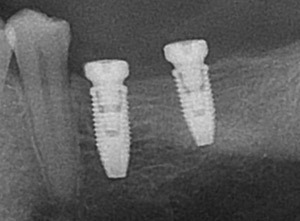

- Cas 4 : Agénésie dentaire

La croissance osseuse se termine chez ce jeune homme. Après une préparation orthodontique, l'indication implantaire pour les 2 incisives latérales maxillaires a pu être posée.